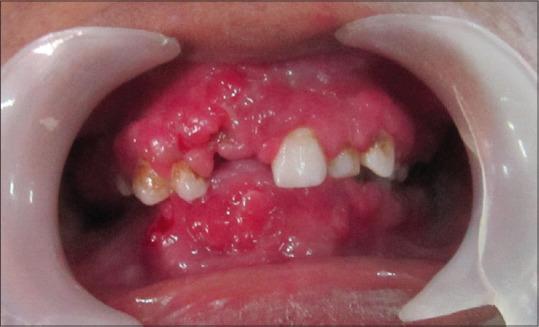

Gingival enlargement can be multifactorial; it can be due to nutritional deficiency or can be because of several drugs. Poor oral hygiene may further worsen the gingival hyperplasia, because of which the patient may have difficulty in chewing the food, and the speech may get affected. It may end up in psychosocial stigma for the patient as the patient is even neglected by friends or relatives due to poor oral hygiene and horrifying look of gingival overgrowth. Here, we report a case of gingival enlargement in a 22-year-old married female. The enlargement was massive, such that the teeth were barely visible in the anterior mandible. Based on history and histological findings, the case was diagnosed as idiopathic gingival enlargement. Conventional gingivectomy was planned. The patient was kept on the maintenance phase, and no recurrence was recorded. During the whole treatment phase, there was a notable change in the behavior of the patient. Surgical correction and subsequent maintenance of good oral hygiene may improve the disease condition, which in turn helps the patient in not only improving the aesthetics but also results in better social acceptance.

牙龈肿大可能是多因素导致的;它可能是由于营养缺乏,也可能是由多种药物引起。口腔卫生不良可能会使牙龈增生进一步恶化,患者可能因此咀嚼食物困难,说话也可能受到影响。由于口腔卫生差和牙龈过度生长的可怕外观,患者甚至可能被朋友或亲戚忽视,最终可能导致心理社会耻辱感。在此,我们报告一例22岁已婚女性牙龈肿大的病例。肿大非常严重,以至于下颌前部的牙齿几乎看不见。根据病史和组织学检查结果,该病例被诊断为特发性牙龈肿大。计划进行传统牙龈切除术。患者处于维持阶段,未记录到复发情况。在整个治疗阶段,患者的行为有显著变化。手术矫正以及随后保持良好的口腔卫生可能会改善病情,这不仅有助于患者改善美观,还能使其更好地被社会接受。